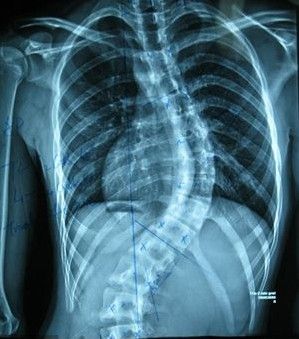

强直性脊柱炎的症状包括哪些

第二、疾病还会造成患者的下腰部位出现不适,同时还有的会伴随僵硬,这种情况一般发展的较为缓慢,患者不能准确找到发病的部位,有的时候,这种病症还会延伸到臀部,如果疼痛的部位开始演变为双侧发展的话,那么其治疗的难度就会更加严重,因此说无论怎样患者都应该坚持早治疗,这样才能尽快把病情给控制住!

第三、患者还会有四面的关节同时出现炎症,较常见的就是髋部关节,这种炎症常常会是双侧同时发作,发病的时候,往往较为缓慢,患者很快就会出现关节的病变,其次发病的部位就在肩部,有些患者还会有关节的压痛点出现,这样一来不仅症状的情况会加重,还会造成医生的治疗进度减慢,所以说患者需要早日解决才是!